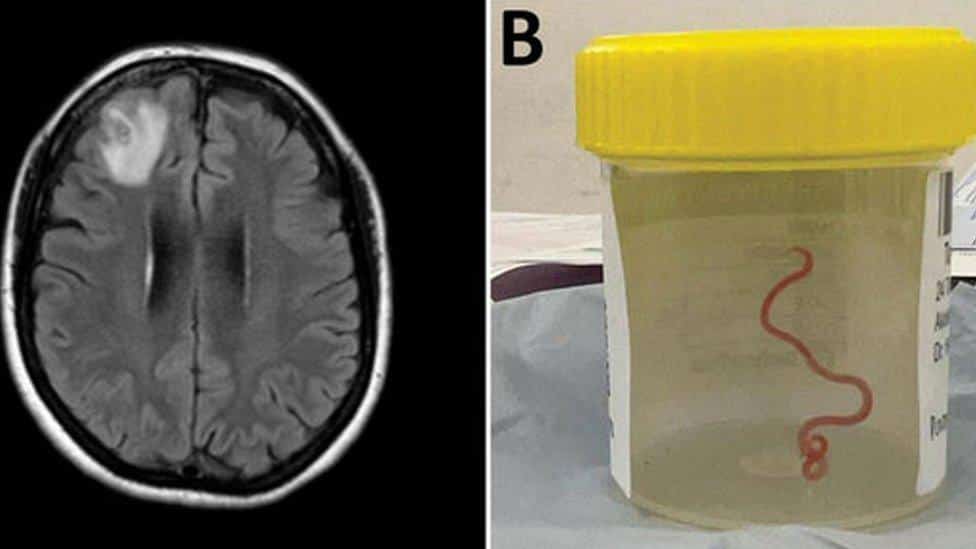

GUSANO VIVO ES EXTRAÍDO DE CEREBRO DE MUJER

En un caso nunca antes documentado en el mundo, científicos informaron que encontraron un gusano vivo de 8 cm en el cerebro de una mujer en Australia. La “estructura en forma de cuerda” fue extraída del lóbulo frontal lesionado de la paciente durante una cirugía en Canberra el año pasado. “Definitivamente no era lo que esperábamos. Todo el mundo quedó